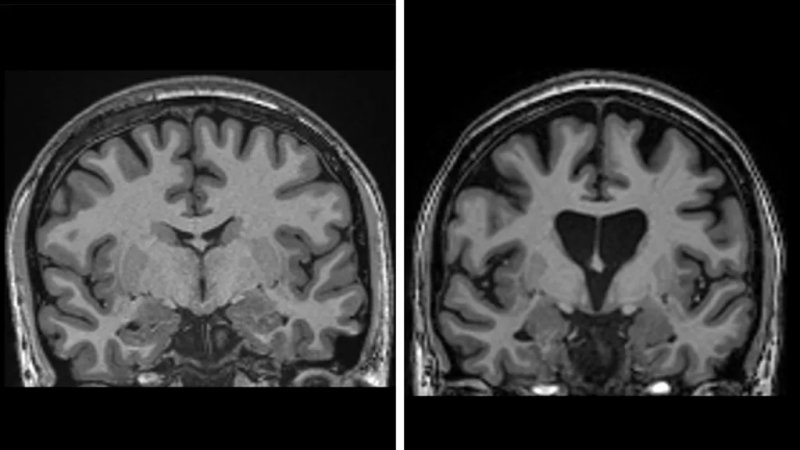

The trial involved 29 patients, with some previously unable to walk or work now showing dramatic improvement. Brain scans confirmed that neuron loss had slowed, and levels of neurofilaments, markers of cell death, were lower than before treatment.